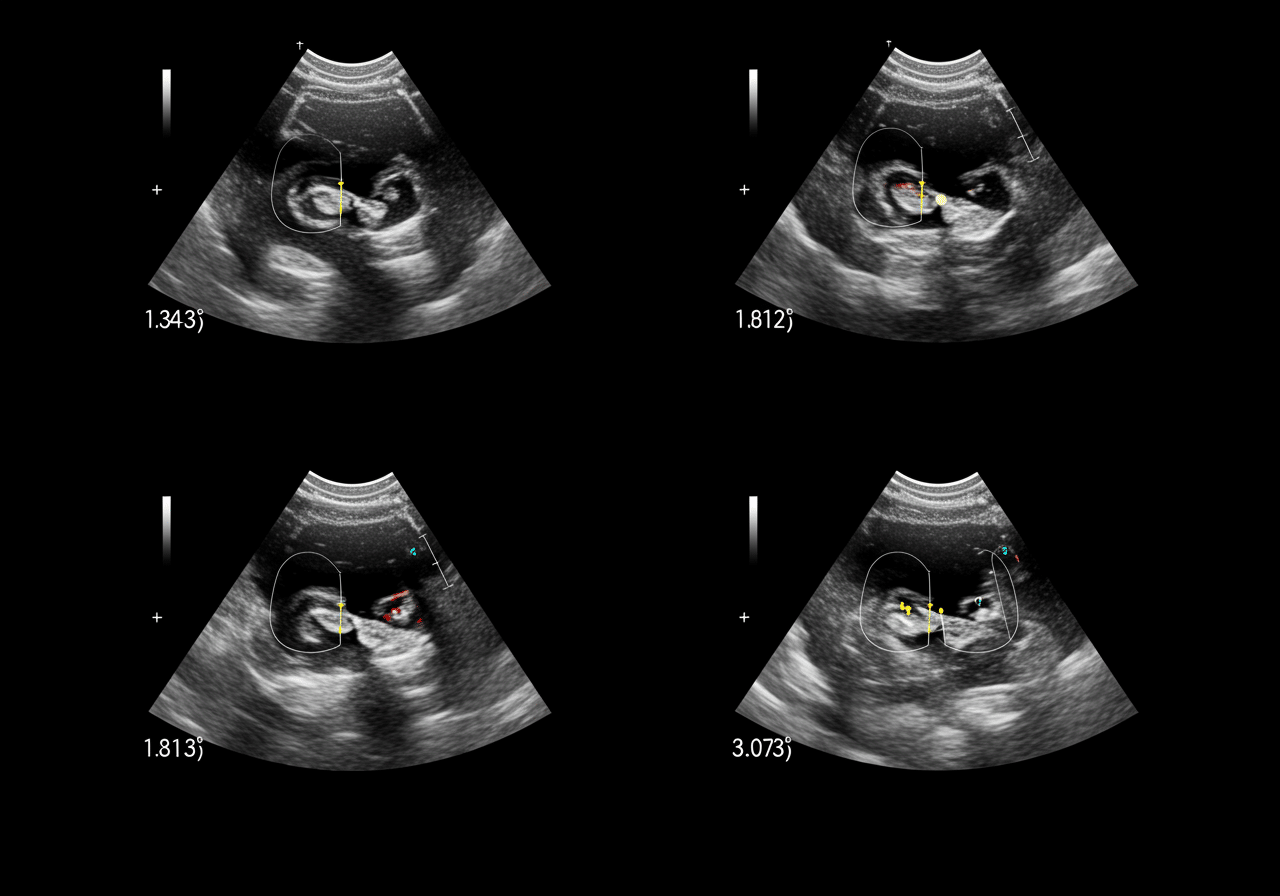

According to the American College of Emergency Physicians, the Focused Assessment with Sonography for Trauma (FAST) exam has revolutionized trauma care by detecting hemoperitoneum with 86-97% sensitivity in unstable patients, enabling immediate surgical decisions without CT delays that increase mortality[5]. The critical difference between survival and death in trauma often comes down to seeking appropriate ultrasound (FAST) for internal fluid, DVT evaluation, or gallbladder inflammation within minutes of injury for FAST exams, within 4 hours for DVT diagnosis preventing pulmonary embolism, and within 24-48 hours for acute cholecystitis preventing gangrenous gallbladder and sepsis[6]. Our trauma emergency capabilities include immediate bedside FAST examination evaluating Morrison’s pouch, splenorenal recess, pelvis, and pericardium, with positive findings triggering trauma activation and emergency laparotomy coordination.

• FAST Exam: 0-5 minutes - Bedside four-view assessment (Morrison's, splenorenal, pelvis, pericardium)

• DVT Ultrasound: 0-15 minutes - Compression ultrasound common femoral to popliteal vein

• Gallbladder: 5-20 minutes - Right upper quadrant ultrasound with Murphy's sign assessment

• Interpretation: Immediate emergency physician findings with surgical consultation

• Treatment: 20-60 minutes - OR coordination, anticoagulation, or admission as indicated